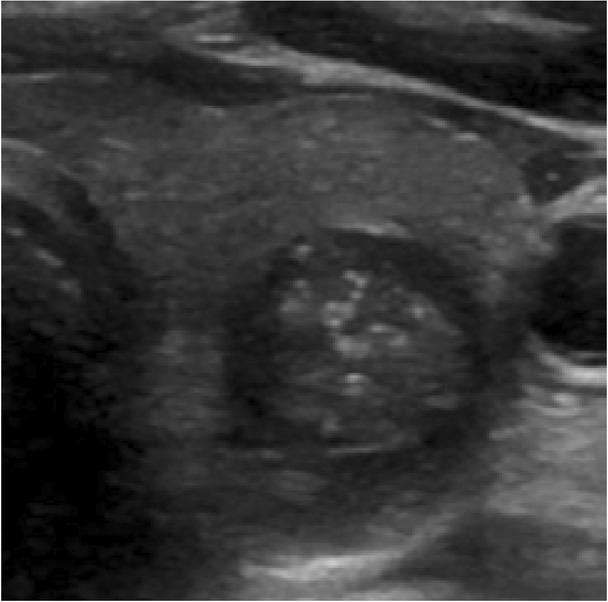

The ACR TI-RADS committee recommends a more conservative selection of wider-than-tall, or alternatively, not taller-than-wide (+0 points) (Fig. 8)(4). It is important to note that the shape of the nodule should usually be assessed on the transverse plane of the thyroid gland(3). The ACR TI-RADS committee notes that it may rarely be appropriate to assess this characteristic in the sagittal plane if the nodule is obliquely oriented in that plane(4).

Fig. 8

Transverse greyscale sonographic image of a completely round thyroid nodule (anteroposterior measurement equals transverse measurement). The more conservative ‘wider-than-tall’ description should be selected for scoring